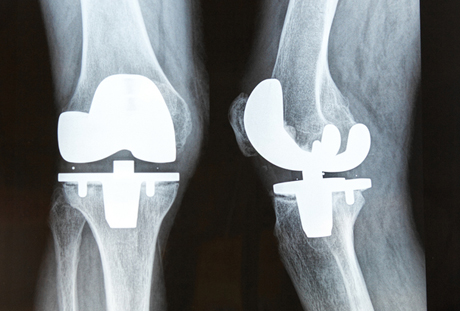

The knee is one of the most complex joints in the human body. It has to sustain the weight of the entire body and must endure repeated impacts from walking and running. At work, it must endure even heavier loads.

Modern knee replacement surgery [right] used hi-tech materials to maintain flexibility and weight-bearing. But the ancients did not have this technology. A failure of the knee joint would mean that the vistim would be confined to either a bed or chair and would likely endure severe pain if the limg was moved. The most effective remedy was to mmobilize the joint, as was done to Usermontu. This surgery would have allowed the patient to walk with a cane and would have prevented continuous pain.